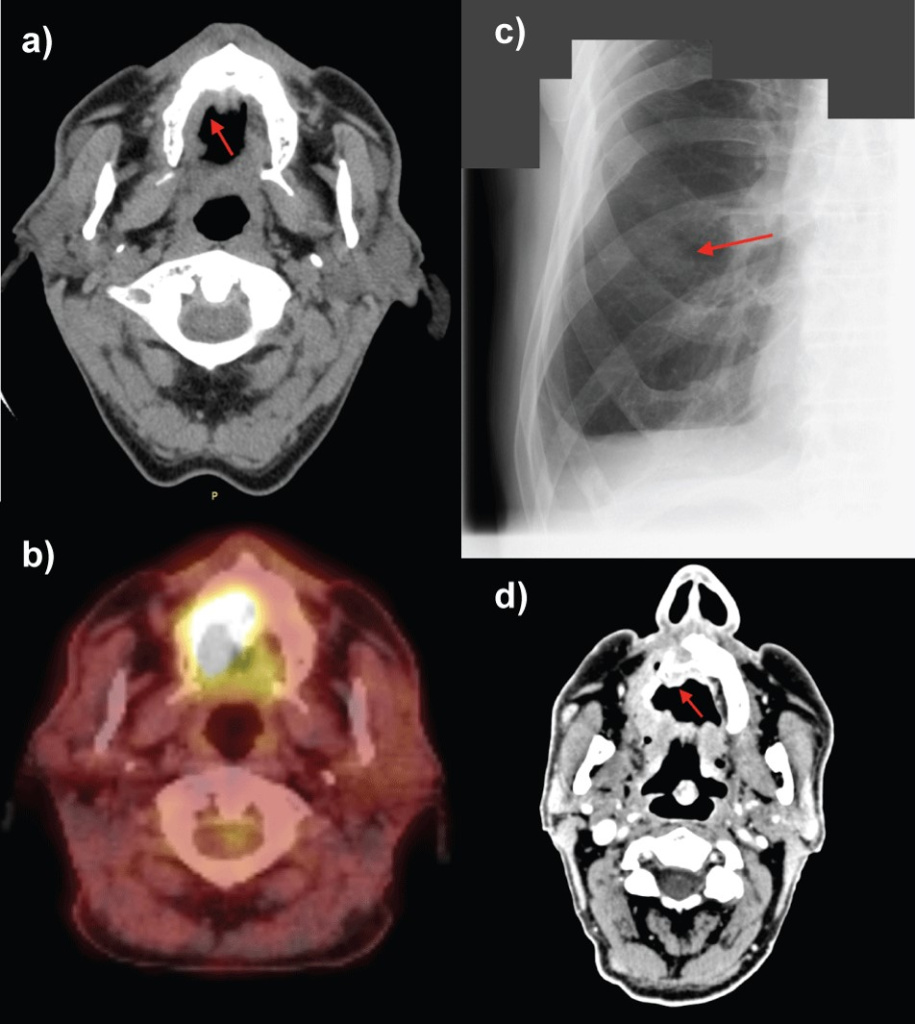

Лечение

При терапии такого заболевания применяется мультидисциплинарный, то есть комплексный подход. Применяются следующие методики лечения в различных сочетаниях:

• хирургическое вмешательство, при котором удаляется первичный очаг, а далее решается вопрос о необходимости шейной лимфодиссекции (удалении лимфоузлов на шее);

• адъювантная лучевая терапия;

• адъювантная химиотерапия;

• иммунотерапия (если подтверждено наличие мутации в генах BRAF и C-KIT).